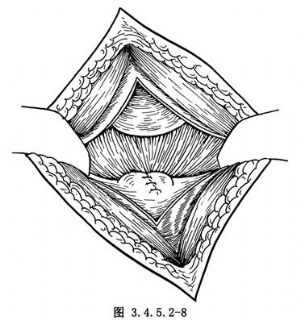

(4)用周圍軟組織覆蓋截骨面並間斷縫合數針(圖3.4.5.2-8)。按層縫合切口,厚敷料適當加壓包紮。